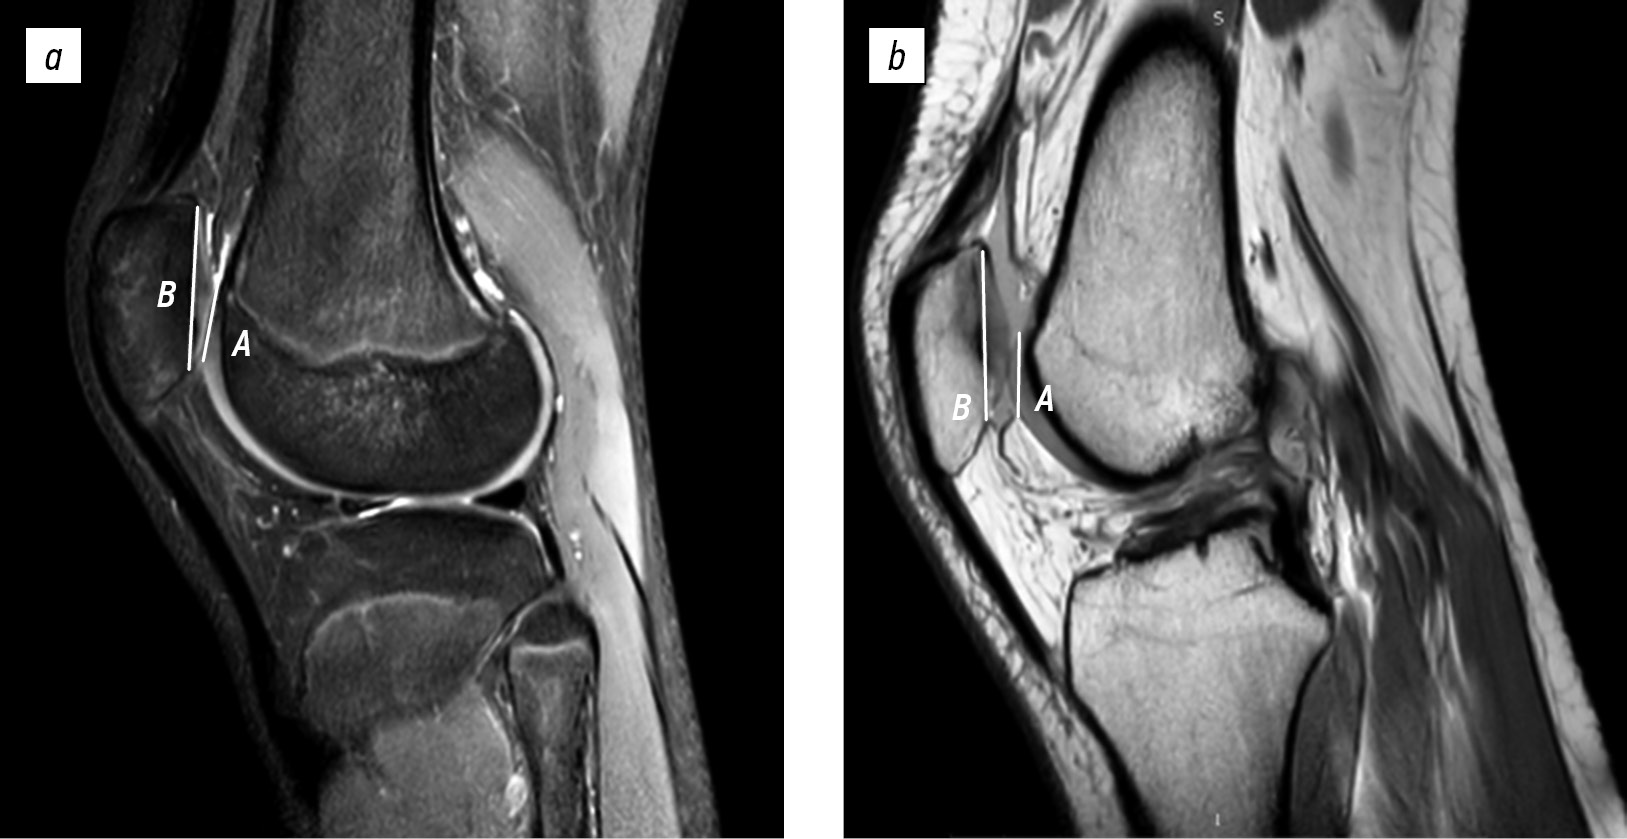

Furthermore, the depth of the trochlear groove was assessed using axial slices. The measurement was performed using the formula ([A + B/2] − C) proposed by Pfirrmann et al. [14]. Distances A and B were defined as the maximal anteroposterior measurements from the posterior aspects of the femoral condyles to the subchondral bone of the trochlear groove at the lateral and medial sides, respectively. Distance C represented the minimal anteroposterior distance from the deepest point of the trochlear groove to a line parallel to the posterior contours of the femoral condyles (Fig. 3).

Fig. 3. Trochlear groove depth measurement on magnetic resonance imaging in a 16-year-old female with patellar instability: A, maximal anteroposterior distance between the femoral condyles and lateral facet; B, maximal anteroposterior distance between the femoral condyles and deepest point of the trochlear groove; and C, maximal anteroposterior distance between the femoral condyles and medial facet.